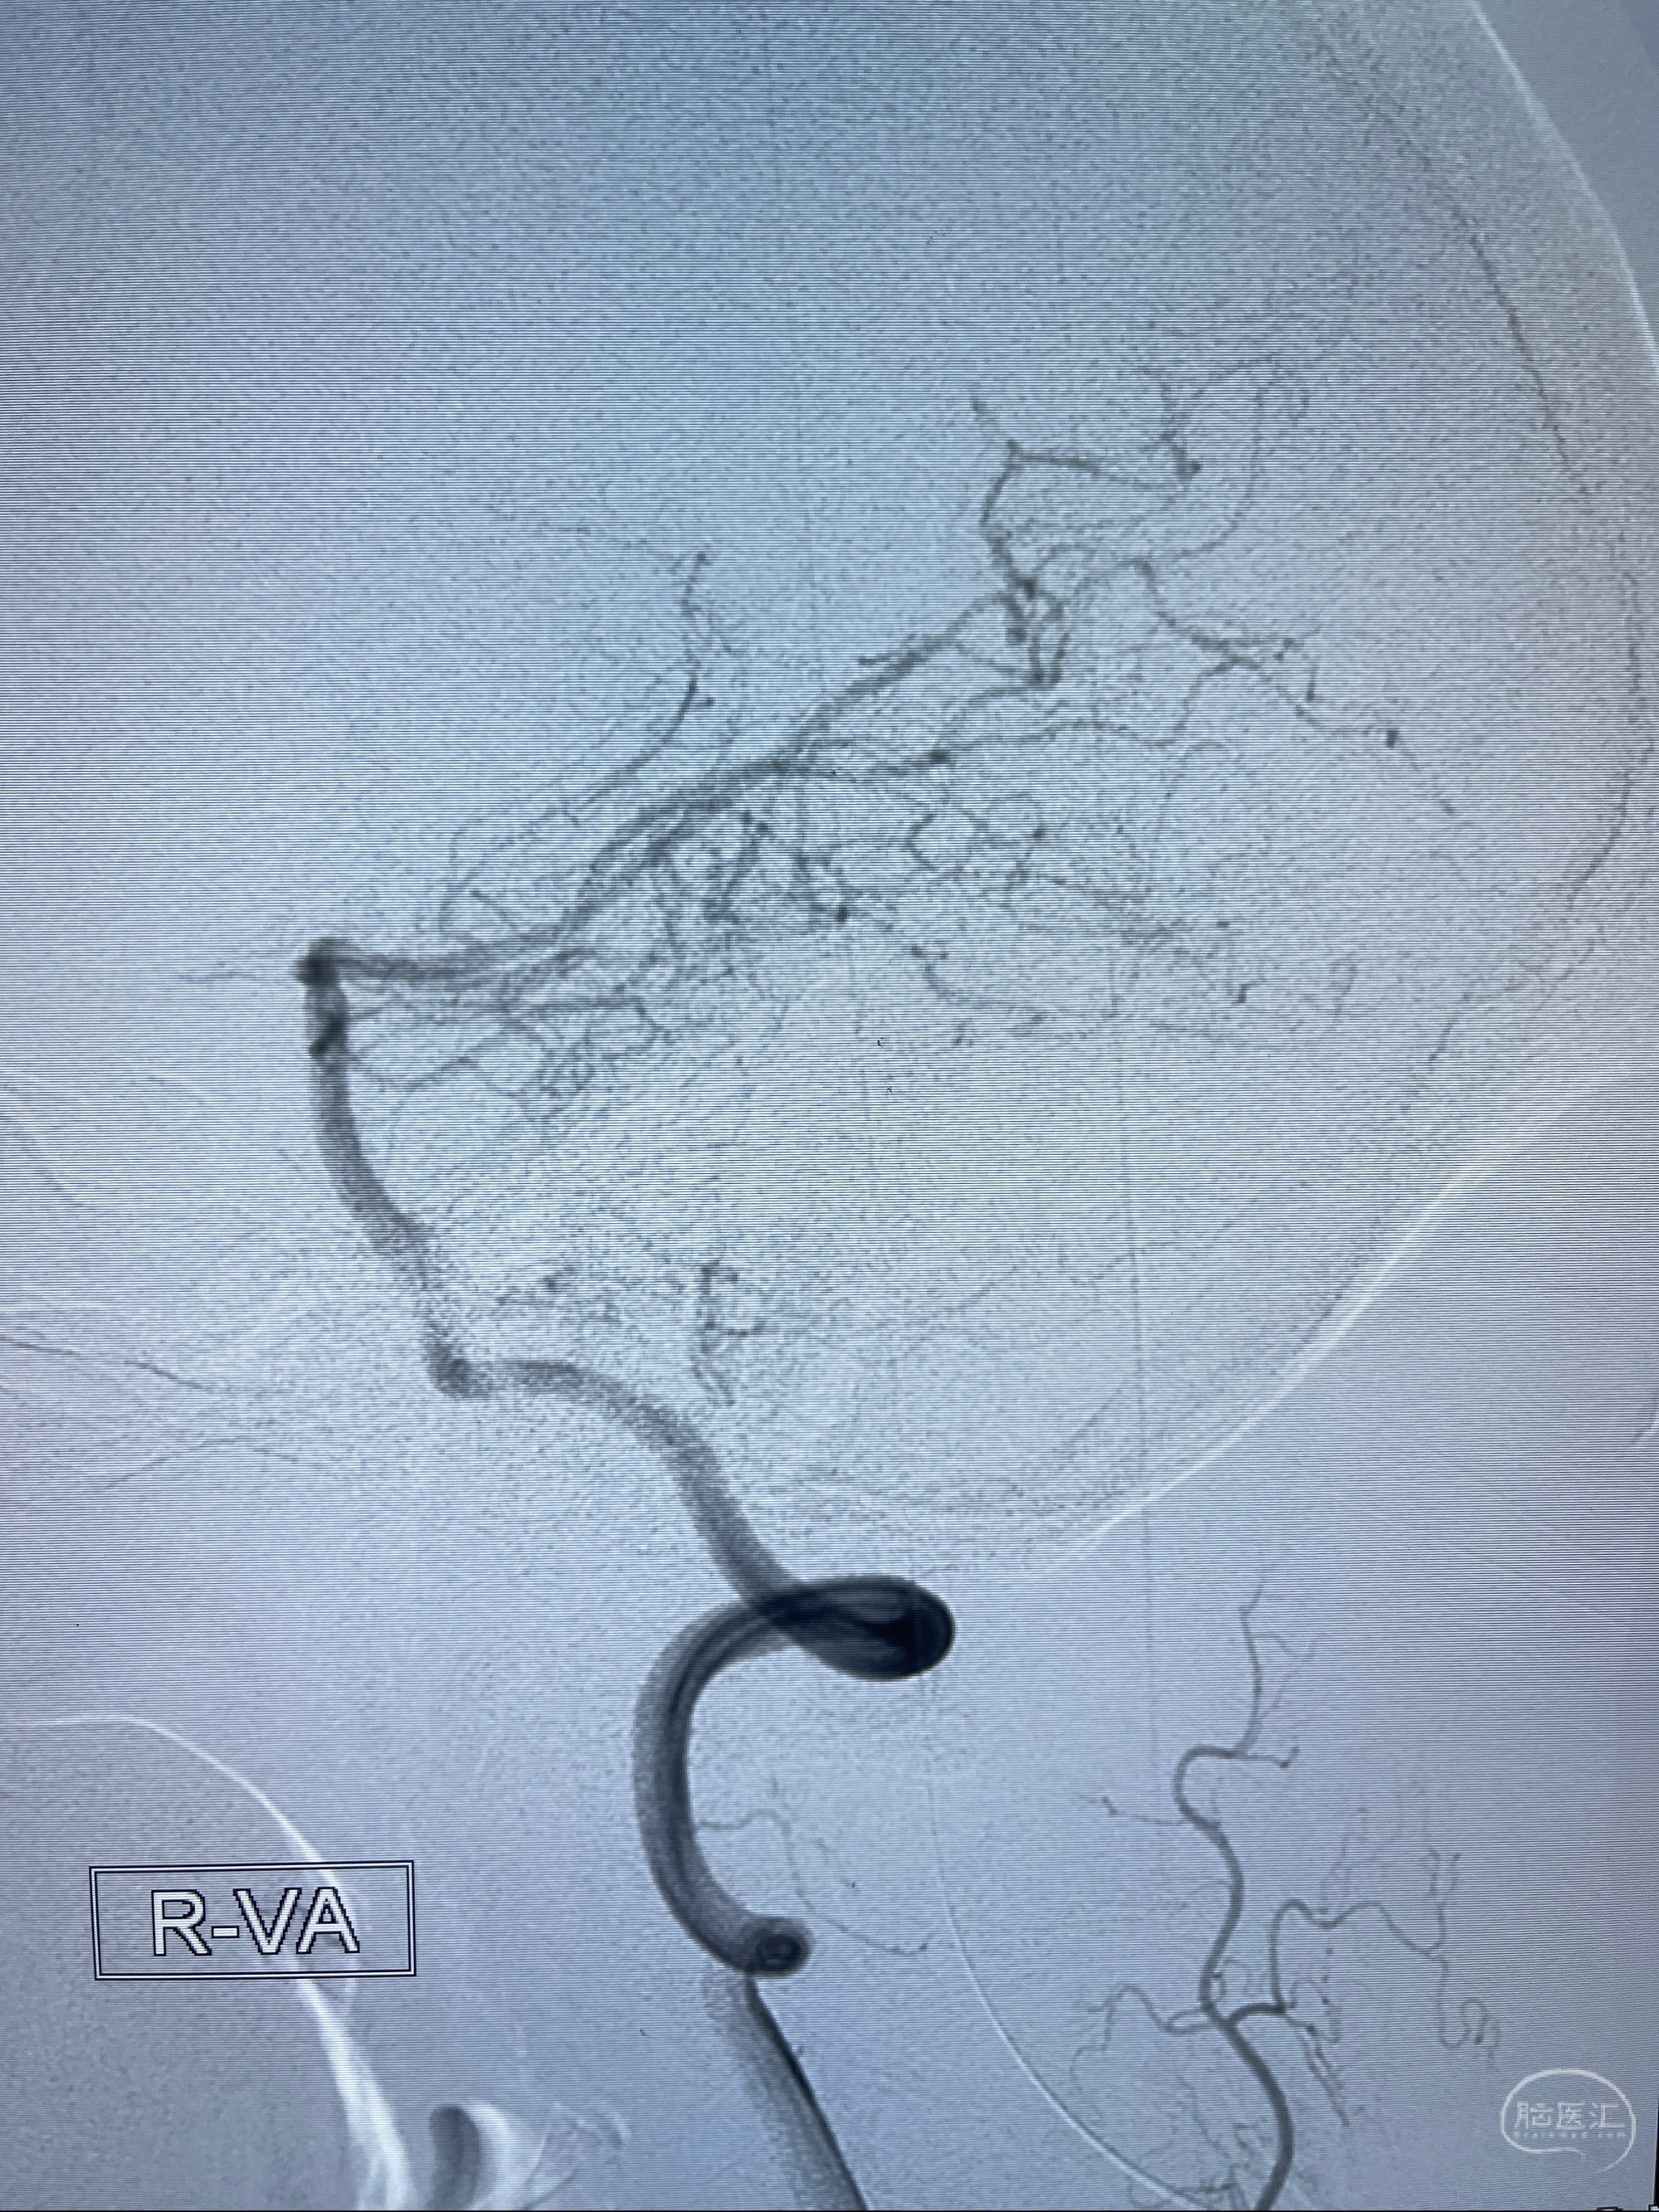

2023-08-14DSA:

左侧大脑中动脉动脉瘤,约2.6-2.8-3.4-2mm大小(瘤颈部、瘤体部、瘤高)